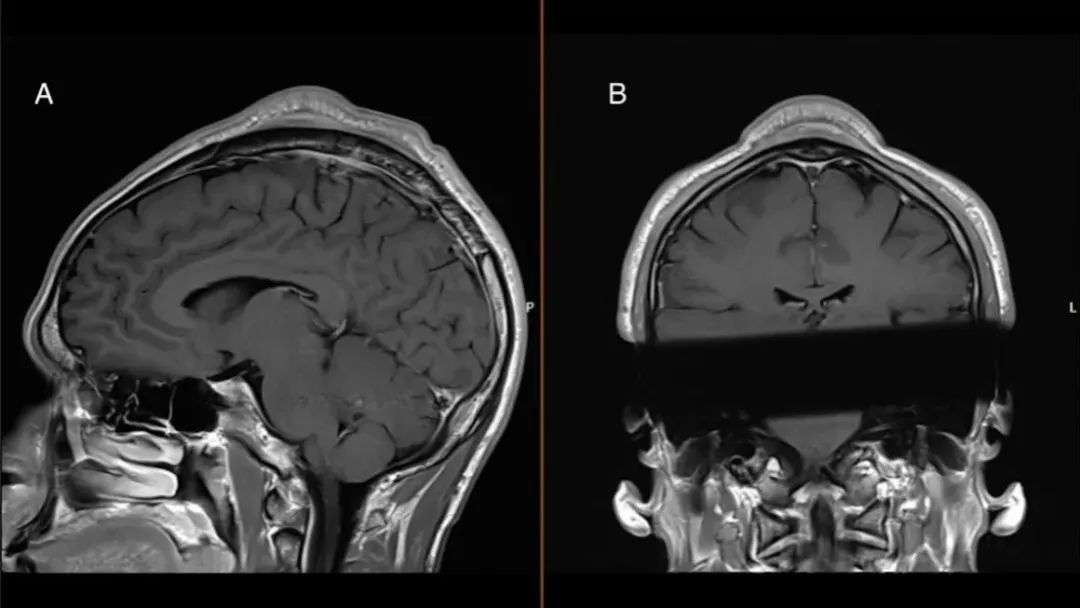

医生在他头顶检测出了一块尺寸约33厘米的肿块,还发现肿块周围的皮肤和组织等也都变厚了,不过幸运的是,肿块并没有发生癌变,通过手术很快就被切除了。

不过肿块周围的皮肤和组织仍然很厚,仔细看手术前后的对比照就能发现,肿块没了头顶确实重新变圆了,但还是略高于正常人。